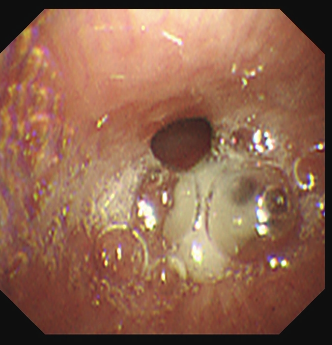

纤支镜下见:右下叶支气管大量脓痰

住院次日,黄善珊主治医师在团队协作支持下,为患者实施电子支气管镜检查。镜下真相令人心惊:右下叶支气管内布满痰栓,一段异物深深嵌顿在右下叶前基底段,被分泌物紧紧包裹。若再不及时取出,极易引发气道完全阻塞、窒息等危及生命的严重后果。凭借团队扎实的技术功底与默契配合,黄善珊主治医师精准定位、轻巧操作,将异物完整取出——众人意外发现,这枚“元凶”竟是一小段酸豆角!